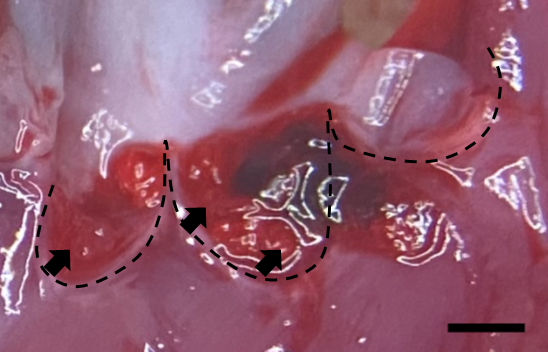

Infective endocarditis (IE) is a prototypical biofilm-associated infectious disease of the cardiovascular system, characterized by a high mortality rate (Fig. 1). Clinical management of IE still relies on prolonged administration of high-dose antibiotics and is often complicated by frequent recurrence. My research has demonstrated that host factors significantly enhance the virulence of IE pathogens. For instance, platelets contribute to biofilm formation and antibiotic resistance in IE pathogens (Fig. 2). Furthermore, aggregates formed between bacteria and platelets stimulate infiltrating neutrophils to release neutrophil extracellular traps (NETs), which in turn activate additional platelets and promote thrombus formation. This cascade contributes to the expansion and maturation of IE vegetations (Fig. 3).

We further demonstrated the critical roles of autolysin (AtlA)-mediated extracellular DNA (eDNA) release and membrane vesicle production in biofilm formation in IE (Fig. 4). In addition, we identified key bacterial virulence factors, including LiaR, PCP, and PrsA, that contribute to eDNA release and membrane vesicle production, both of which promote bacterial biofilm formation in vivo. The underlying molecular mechanisms by which these factors regulate biofilm development will be further investigated (Fig. 5).